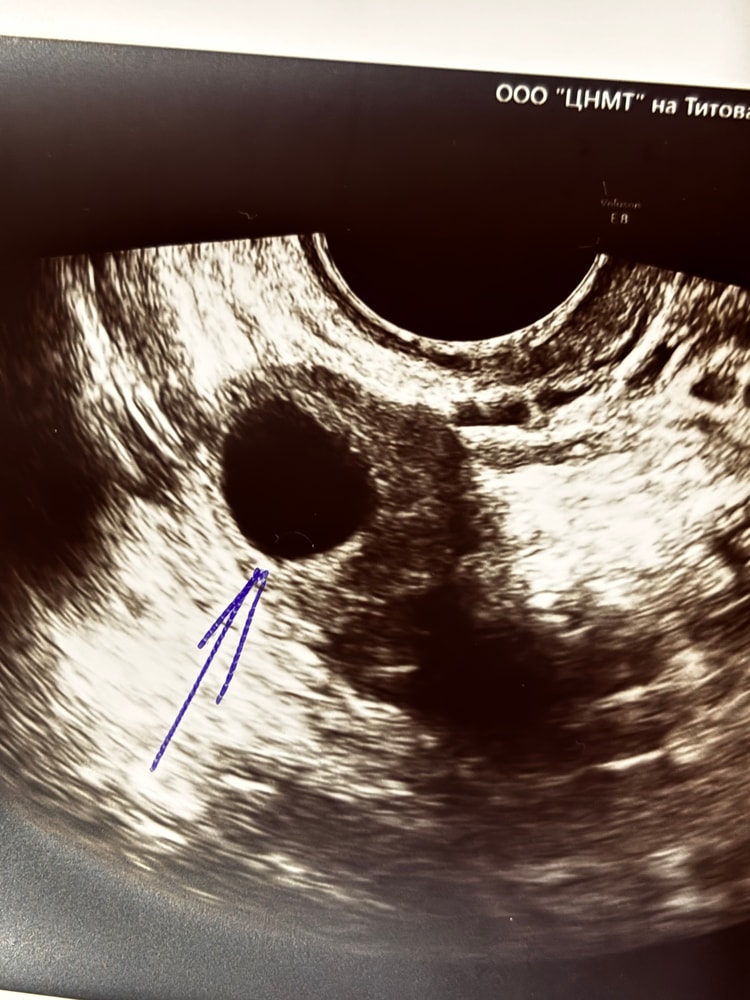

Li → Зачатие УЗИ Нижний Новгород ЖЕЛТОЕ ТЕЛО на УЗИ, ДОМИНАНТНЫЙ ФОЛЛИКУЛ на УЗИ Девочки, подскажите пожалуйста, как выглядит на УЗИ ДФ И ЖТ, может у кого есть фото. Спасибо 🙌 Посмотрите еще 20 записей на эту тему Лучший ответ Лера Мама девочки (11 дней) Москва Жт 0 13.11.2025 Ответить Li Нижний Новгород Лера, спасибо большое 0 13.11.2025 Ответить Лера Мама девочки (11 дней) Москва Дф 0 13.11.2025 Ответить Помогите разобраться какой дпо Пя 5,8 на 6.1 неделе Похожие записи 4 доминантных фолликула на клостике!!! Нет доминантного фолликула, эндометрий 5.3. ЖТ и доминантный фолликул 2 Протокол и доминантный фолликул 13 мм на старте Желтая моча у младенца Чаты Беременных Выберите чат: Июлята-2026 Августята-2026 Сентябрята-2026 Октябрята-2026 Ноябрята-2026 Декабрята-2026